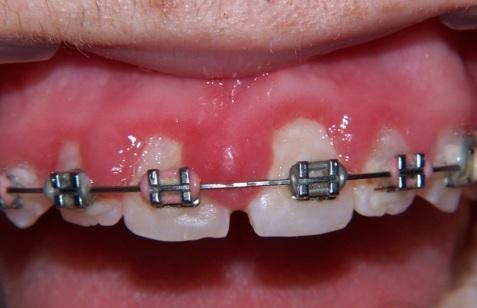

- Parodontologia

- Mucositi-perimplantiti

Applicazioni Cliniche